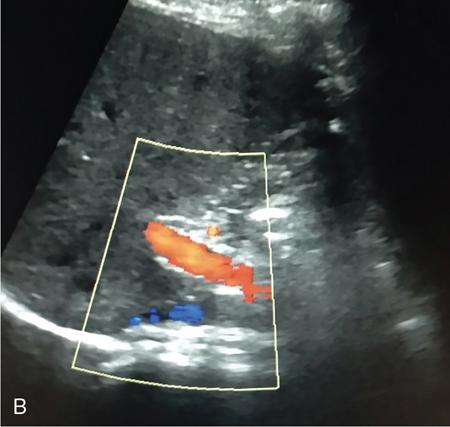

Samarjit Ghuman, Seema Sud, Deeksha Rastogi, Swapnil Sheth, T.B.S. Buxi PLAIN RADIOGRAPHY FOR HEPATOBILIARY IMAGING The diagnostic imaging techniques for hepatobiliary imaging can be intimidating with many techniques/modalities providing the information desired. The job of the diagnostic radiologist includes being familiar with the available choices and pick the ‘best fit’ keeping in mind the pros and cons of each modality, which includes plain X rays, Contrast studies using plain X rays and fluoroscopy, Ultrasound includiojng Doppler and Ultrasound elsastography, CT including multiphase CT and MRI and MRI elastography. Understanding the strengths and weaknesses of every modality as well as the ability to tailor each study individually will help to optimise patient cares. The abdominal radiograph is performed almost exclusively in the supine position and in the AP (anteroposterior) projection. In case of acute abdomen, an erect chest radiograph should also be performed to look for free air under the diaphragm. The standard abdominal radiograph should extend from the diaphragm to the inferior pubic rami, and includes the lateral abdominal wall musculature. Routinely no preparation is required for abdomen radiograph done for hepatobiliary imaging. The radiograph has limited soft-tissue contrast, however, the liver being the largest intra-abdominal organ, casts a perceptible shadow. The margins of the liver can indirectly be seen by outline of adjacent organs like lung, hemidiaphragm, pro-peritoneal fat line, kidney and gas shadows of stomach/colon. The right lobe is seen better than the left lobe of liver. The following pathologies may be visualized on the plain radiograph of the liver. Liver enlargement Liver mass Calcification Increased radiodensity of the liver Decreased radiodensity of the liver An ultrasound is the first line investigation; however, a radiograph may be done for routine evaluation of abdominal pain. The following pathologies may be seen on plain radiograph of the biliary tree. Calculi and Calcifications Gas ULTRASOUND OF HEPATOBILIARY SYSTEM Ultrasonography (USG) is the initial imaging modality of choice for scanning hepatobiliary system. USG is accurate and has high sensitivity and specificity in diagnosing biliary pathologies. Table 9.1.1 shows indications of ultrasound in hepatobiliary system. The real-time nature of ultrasound lends itself to demonstrate mobility of calculi and sludge and the sonographic Murphy sign can easily be elicited during scanning. The main disadvantage is operator dependence, patient’s body habitus, presence of gas which can obscure the visualization of organs, overlying bandages in a postoperative patient and incomplete evaluation in a nonfasting state. USG of upper abdomen should be done after 6–8 hours of overnight fasting. Milk and fatty food should be avoided as they cause contraction of the GB and may cause the GB walls to appear thickened. History of previous surgery, especially cholecystectomy should be elicited. The patient may be positioned in supine or left lateral decubitus position. The GB can be scanned from a high/lateral view, looking through the ribs in supine position or through a sub-costal view in left lateral decubitus position. Position of patient may be changed to demonstrate mobility of structures. The GB is an anechoic structure which is located in the GB fossa along the posterior and inferior aspect of the liver. It has a fundus, body and a neck. It should always be examined in at least two planes (Fig. 9.1.6A and B). The wall of the normal GB should measure 3 mm or less and pathological GB wall thickening can be due to cholecystitis or a neoplastic aetiology. Calculi appear as mobile hyperechoic foci, with distal acoustic shadowing. Other pathologies include polyps and sludge which can be differentiated on the basis of their mobility. The CBD measures less than 6 mm in diameter with increase in the diameter with patient’s age and after cholecystectomy. The CBD is usually scanned in an oblique subcostal plane with the patient in the left decubitus position (Fig. 9.1.7). Dilatation of the intrahepatic biliary radicles is readily assessed with USG and normal intrahepatic biliary radicles are usually not appreciated on USG. Ultrasound of the liver, broadly, is done to assess the size, surface (smooth, coarse or lobulated) parenchymal echogenicity (increased or decreased) vascularity and for presence and evaluation of intrahepatic masses or fluid collections. The liver is divided into right and left lobes by plane of middle hepatic vein which passes through GB fossa and notch of IVC (Cantlie Line). Couinauds classification is the most commonly used system for liver segmental anatomy and described liver into eight functional segments. It is based on distribution of portal and hepatic veins. Every segment has its branch from portal vein, hepatic artery and bile duct (Fig. 9.1.8). Curvilinear transducer (3–5 MHz) is used for routine examination of liver and GB (Fig. 9.1.9). A high-frequency linear transducer (9–11 MHz) (Fig. 9.1.10) can be used to look for subtle irregularity of the liver surface for early Cirrhosis and fine details of GB wall. The liver is scanned in deep inspiration, which causes inferior movement of liver, so that superior borders of the liver are well visualized. Supine position is used for the size of the liver. The measurement is made in sagittal mid clavicular position on right side, in craniocaudal dimension. It is taken from diaphragm to the lower end of the liver. It should be <16 cm and varies with age and sex. The liver is divided into four vertical sectors by three hepatic veins and plane of bifurcation of portal vein divides these 4 sectors in to 8 segments. The right hepatic vein creates vertical plane in the right lobe separating segments V and VIII (anterior) from VI and VII (posterior). The portal vein bifurcation creates a transverse plane and divides these segments into superior (VII, VIII) and inferior segments (V, VI). The left hepatic vein divides the left lobe into medial (IVa, IVb) and lateral sectors (II, III). The left portal vein divides left lobe into superior (Iva, II) and inferior segments (III, IVb). The middle hepatic vein separates medial segments of left lobe (IVa, IVb) from anterior segments of right lobe (V, VIII). Ligamentum teres separates segment III from IVb. Ligamentum venosum separates segment I from IV and II. Cystic duct is an anechoic tubular structure which connects neck of the GB to the extrahepatic biliary tree. In long axis view of GB, the neck of the GB is related to main lobar fissure which appears as a linear echogenic line which runs obliquely between neck of GB and right portal vein. In the right oblique sub coastal view CBD is seen anterior and parallel to portal vein. A series of standardized sections or views may be obtained for liver scanning. Transverse Subcostal View: In this view the probe is angled cephalic and placed transversely under the ribs on the right side and portions both lobes of the liver can be seen (Fig. 9.1.11). Mid Transverse View (Fig. 9.1.12) in this transducer is kept in transverse plane in the midline below the xiphisternum. It visualises the liver in an inferior to superior transverse oblique plane and portions of both lobes of liver can be seen along with right and left portal veins. This view is obtained by angling the transducer superiorly toward the hepatic venous confluence. In this view, we can see the three hepatic veins joining the IVC. Right Parasagittal View for Both Right Lobe and Kidney: This view allows assessment of inferior right lobe of liver. It also allows assessment of relative echogenicity of liver and renal cortex as both are seen together in the same image. Normal liver parenchymal echogenicity is greater than renal cortex and less that renal medulla (Fig. 9.1.14). Parasagittal Right MidClavicular View: In this transducer is kept in sagittal plane in right midclavicular line, and oriented supero-inferiorly. This is the standard view for assessing craniocaudal span of liver (Fig. 9.1.15). Parasagittal View for the Left Lobe: For evaluation of left lobe of liver and lateral segments (2 and 3) (Fig. 9.1.16). This view is obtained along the direction of the main portal vein. CEUS of the liver is done to evaluate Focal Liver Lesions and complements traditional B mode ultrasound and Doppler study. It is a simple, accurate and cost-effective tool complimenting indeterminate CT and MRI findings or for characterization of lesions in patients who cannot receive CT/MRI contrast and can be used in patients with compromised renal function, with minuscule risk of side effects. As CEUS is real-time, microvasculature can be studied along with tissue perfusion kinetics. Indications and uses of CEUS: Contrast agents and technique: Interpretation: Contrast-enhanced ultrasound of a hepatic hemangioma in different phases (Fig. 9.1.19). Limitations of CEUS: Liver elastography is a noninvasive method for diagnosing liver fibrosis. Liver fibrosis is induced by chronic liver disease leading to cirrhosis and liver cancer. Liver biopsy is the gold standard for diagnosing the degree of fibrosis and for staging but it is an invasive method. Elastography helps in analysing the elasticity or the stiffness of the tissue. A stiffer liver tissue indicates fibrosis or chronic liver disease. ARFI is based on the principle of measuring Shear wave velocity. Short duration acoustic pulses which are generated in the tissue and these give rise to shear waves which travel, perpendicular to the ultrasound beam. These shear waves cause tissue displacement followed by recovery. This displacement and recovery depend on tissue stiffness. To monitor these shear waves US beams of low intensity are emitted continuously parallel to the main beam along with the push pulses, and these beams can gather data regarding the tissue stiffness. The shear waves cause tissue displacement and this tissue then recovers from the impulse. From this data the degree of tissue stiffness can be obtained which is displayed either as a map or quantitatively where tissue elasticity is expressed as shear wave velocity measured in meters per second. F0, normal; F1, enlarged fibrotic portal tract; F2, periportal/initial porto-portal septa with intact architecture; F3, architectural distortion with no obvious cirrhosis; F4, cirrhosis. It is also known as Transient Elastography (TE) and works on the similar principle as ARFI, the difference being that B mode ultrasound image is not produced. DOPPLER OF PORTAL VEIN The portal vein divides at the portahepatis into right and left branches. The right portal vein divides into anterior and posterior branches, and the left portal vein divides into medial and lateral branches. Portal vein shows a continuous, forward low-velocity flow (15–28 cm/s) on colour Doppler scanning. The flow is hepatopetal, that is, towards liver and is red in colour as it is flowing towards the transducer. It has an undulating pattern and shows respiratory variation with increase flow in inspiration. It may reflect cardiac variation and shows postprandial increase calibre and flow in healthy individuals. Normal Doppler waveform of portal vein (Fig. 9.1.22). Portal hypertension can be defined as elevated pressure within the portal venous system resulting in impaired blood flow through the liver. INTRAOPERATIVE PANCREATIC AND HEPATIC ULTRASOUND Intraoperative ultrasonography of the pancreas was first described in 1980 by Lane and Glazer. It is an important technique for guidance of both open and laparoscopic surgical procedures of the pancreas. As the transducer is in direct contact with the organ of interest, with no interference with air of adjacent soft tissue, it provides good resolution. It is considered superior to CT and MRI in assessing the intraoperative tumour resectability and vascular invasion and guiding resection. Indications and uses For intraoperative US during open surgical procedures, a high-frequency linear-array transducer or the hockey stick transducer (Fig. 9.1.23) are used which create high-resolution detail of the exposed pancreas. The side-fire curved linear-array transducer is effective for obtaining a wider view of the pancreas and its surrounding structures and for scanning the liver. Intraoperative hepatic ultrasound gives the real-time visualization of the hepatic anatomy and aid for surgical planning and making decision during surgery. Indications and uses Transducer and technique Limitations MULTIDETECTOR CT OF THE HEPATOBILIARY SYSTEM AND CHOLANGIOGRAPHY The cross-sectional plane of the patient is denoted as the x/y plane. The plane along which the table moves is the ‘z’ plane. Multidetector CT denotes more than one detector along the Z-axis, with the latest machines having up to 320 and now even 640 rows of detectors. This provides CT with very fast, high resolution, isotropic images which can be reconstructed in any plane or even curved planes. MDCT scanners can comfortably scan the entire abdomen in 10 seconds or less, thereby allowing visualization of different phases of contrast enhancement. Contrast Media (CM) after administration gets distributed from the intravascular compartment into the interstitial spaces. Intravascular arterial enhancement (for angiography) and parenchymal enhancement have different kinetics. Parenchymal enhancement is directly proportional to total iodine dose being administered and inversely proportional to weight, which is a marker of extracellular volume into which contrast redistributes. Rate of iodine administration has no effect on degree of parenchymal enhancement. As a general rule approx. 500–600 mg of iodine/kg body weight achieves adequate hepatic parenchymal enhancement. For a 60 kg adult, this translates into approx. 100–120 mL of contrast containing 300 mg of iodine per mL. Intravascular or arterial enhancement is controlled by rate at which iodine is administered (flow rate and iodine concentration of CM) iodine flux and duration for which contrast is administered longer injection also leads to better overall arterial opacification due to recirculation effects. This principle is made use of while performing abdominal CT Angiography. Higher iodine delivery rate per unit time using a higher iodine concentration contrast medium also improves conspicuity of vessels and hypervascular lesions such as HCC. For identical parameters, difference in arterial enhancement between patients is dependent on cardiac output with enhancement being inversely proportional to cardiac output. For optimal imaging and enhancement, in multiphase imaging and angiographic studies, contrast material administration and parenchymal or vascular enhancement must be synchronized with CT data acquisition. The two main methods are: Test bolus technique: A test dose of contrast is given and the time to peak enhancement is measured in a ROI placed in a target vessel this information can be used to tailor CT acquisition. Automated bolus Triggering: ROI is placed in target vessel (usually aorta at level of diaphragm) on a plain image. While CM is injected, a series of low dose scans is obtained through the ROI. When the density of contrast reaches a predefined threshold (e.g. 150 HU), at time ‘t’ the scan is automatically triggered. The trigger delay after time ‘t’ is a minimum of 2 sec, and can be programmed to any value. Bolus tracking is nowadays the method of choice for planning contrast medium administration and this technique provides more homogenous opacification. Saline chase is recommended in all multiphase protocols. Significant amount of contrast may be present in the peripheral veins after injection of IV contrast and use of saline chaser leads to better vascular enhancement and lower overall contrast dose (Fig. 9.1.24). Using the above, a standard sequence of acquisitions and contrast enhancement techniques can be tailored to the pathology and organ of interest and pre-programmed into the scanner menu, which includes kVp, mAs, pitch, rotation time, slice thickness etc. This is known as a scan protocol. However, these can be modified as necessary. For example, rotation time can be shortened and pitch can be increased for breathless patients to reduce scan times (Table 9.1.4). Multidetector CT is the workhorse of hepatobiliary imaging. It plays a major role in imaging congenital, traumatic, infective, neoplastic and vascular pathologies of the hepatobiliary system. Scans can be obtained with or without intravenous (IV) iodinated contrast material administration. Multidetector CT scanners are capable of imaging multiple phases at different points of time following injection of contrast and provide dynamic imaging due to fast scan times and rapid coverage of the abdomen. Indications for liver imaging include, but are not limited to: Unenhanced Scan: Hepatic fat estimation, radio opaque biliary calculi. Single Phase Scans: Liver abscess, polytrauma, follow up of known oncologic or benign lesions, abdominal pain, suspected cholecystitis. Multiphase Studies: Evaluation of hepatic masses, imaging in cirrhosis, imaging for resectability, liver donor evaluation, malignancy of GB, hepatic venous outflow obstruction etc. CT Angiography of Hepatic Vessels: Trauma, vasculitis, post-operative bleeding and as a part of multiphase studies. Depending on the indication, scanning protocols can be tailored to highlight the suspected pathology and provide relevant answers for further management (Table 9.1.5). The liver has a dual blood supply, most of which is derived from the portal vein. After injection of contrast, until the portal vein provides recirculated contrast material filled blood to enhance the hepatic parenchyma, the hepatic parenchymal enhancement is relatively poor and dependent only on the hepatic artery. The hepatic arterial phase can be divided into an early arterial phase without any portal opacification, a late arterial or portal inflow phase in which there is some portal vein opacification. This is followed by a portal venous phase in which portal and hepatic veins are enhanced (also called the hepatic venous phase in some articles). In addition, an unenhanced/plain scan and an equilibrium phase can also be acquired. Tumour conspicuity of hypervascular lesions was found to be best on the late arterial or portal inflow phase (Fig. 9.1.25). The early arterial phase is seen up to 10 seconds after trigger, and provides ‘angiographic’ images of hepatic arterial anatomy. This phase is used to provide details regarding arterial anatomy and morphology. Later arterial phase 18–23 seconds, portal venous phase 60–70 seconds and equilibrium phase 180 seconds are obtained after trigger. Equilibrium phase images have been shown to increase detection of hepatocellular carcinoma in cirrhotic patients. The portal venous phase is the standard phase for routine chest/abdomen survey and follow up of hepatic abscesses and hypovascular metastases. Single Phase Scan Protocol: Oncologic follow-up, Liver Abscess – For routine single-phase CT, contrast as per body weight can be injected over 40 seconds and scanning can be done after an empiric delay of 70 seconds from the beginning of injection. This protocol provides good parenchymal enhancement and portal and hepatic vein visualization. Plain scan is optional. Dual-Phase Scan Protocol: Hepatic evaluation in patients with malignancies known to have hypervascular metastases – Neuroendocrine tumours, renal cell carcinoma, thyroid carcinoma, (.) melanoma etc. Late arterial Phase 20–22 seconds and Portal venous phase at 60–70. Plain scan optional. Hepatic Resection Protocol: For patients with known hepatic mass being evaluated for resection. Early arterial phase provides pure arterial or angiographic images. It is obtained at 8–10 seconds post trigger followed by portal venous phase at 60–70 seconds. This is required for arterial and venous anatomy and volumetric evaluation if required. Plain scan is not required. In case a hepatic mass needs characterization as well as resectability planning, late arterial and equilibrium scans may also be done. Indications for angiography are further discussed in the section on angiography. The same biphasic protocol using angiography or arterial phase images is used in patients with trauma suspected to have pseudoaneurysms, hepatic artery thrombosis or dissection in transplant recipients, evaluation of living donors and in patients in whom an angiographic ‘road map’ is required prior to intervention. Triphasic or 4 phase scan Protocol: Standard of care for patients with cirrhosis being evaluated for Hepatocellular carcinoma and for patients being evaluated for hepatic mass of uncertain aetiology. Late arterial phase scan: 20–22 seconds, Portal venous scan at 60–70 seconds and Equilibrium scan at 180 seconds. Plains scans are optional. Our institutional practice is to always do plain scans in patients who have undergone hepatic intervention. Plain scans also help to visualize siderotic and steatotic nodules. A further delayed scan is suggested by some authors at 10–15 minutes for characterization of hepatic masses of uncertain provenance. This is particularly useful in cholangiocarcinoma (Table 9.1.6).

Doppler imaging

Sonographic features of portal hypertension